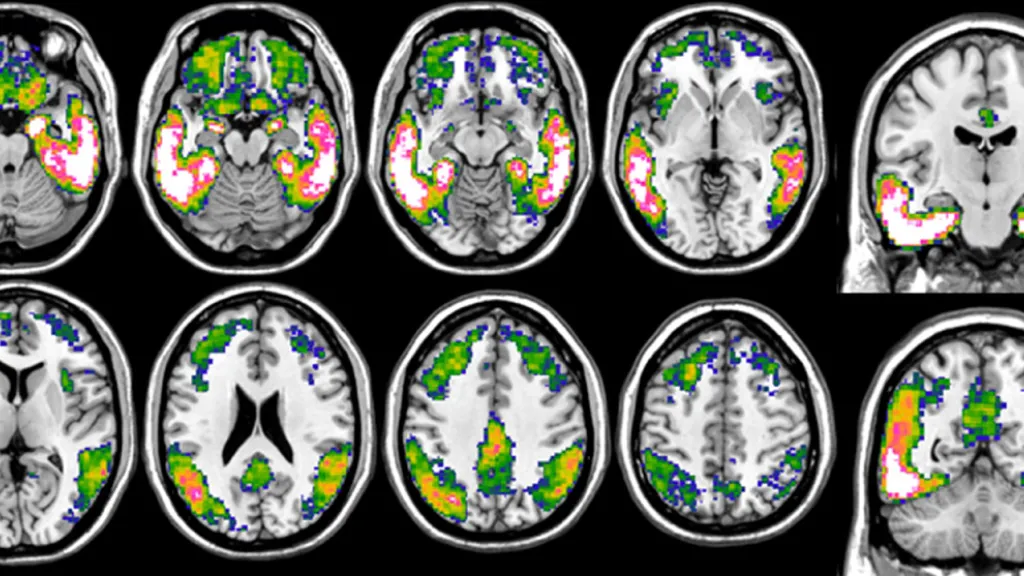

Imaging of the brains of Alzheimer's patients

Wednesday 09 August 2023

Tau-PET: a window into the future of Alzheimer’s patients